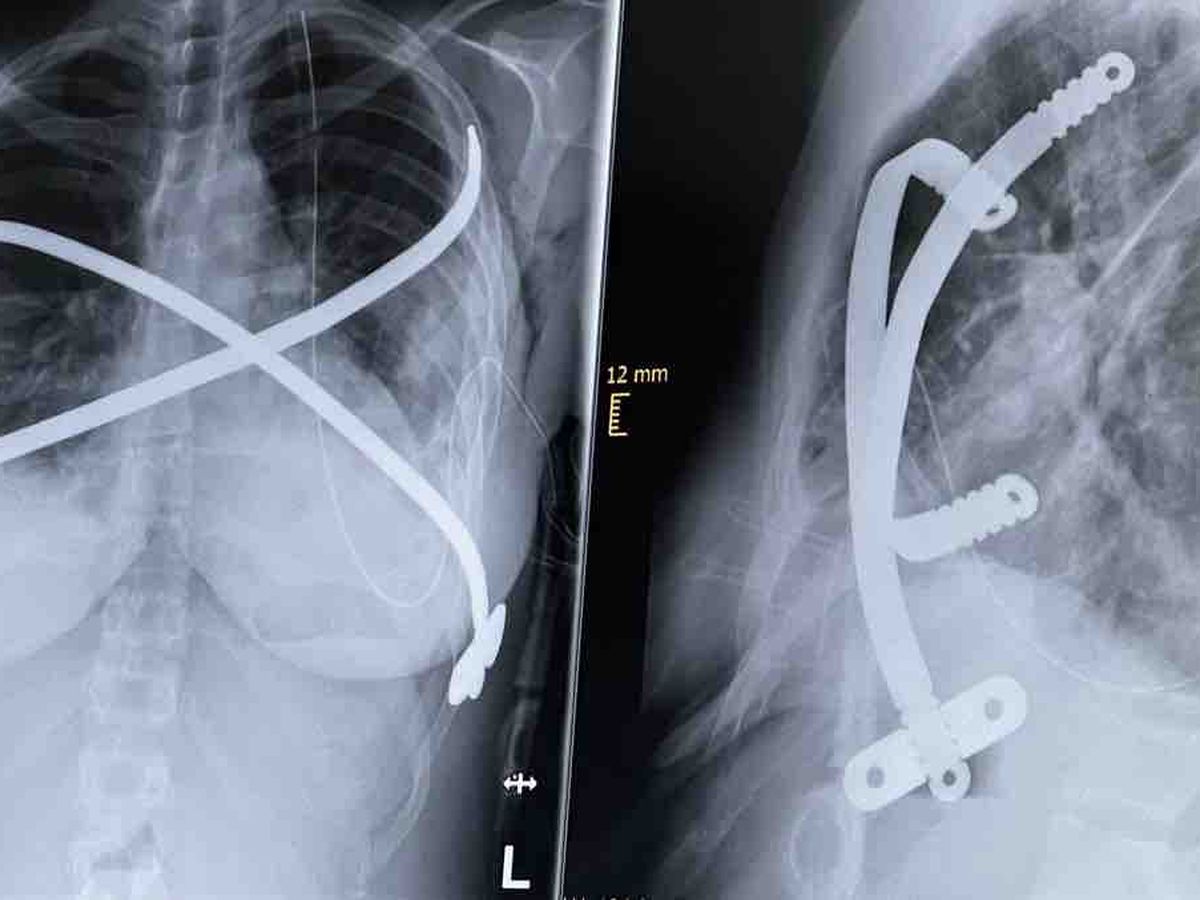

Living in Germany, I spent a transformative year studying at Georgia Southern University in the south of the USA, immersing myself in new cultures and perspectives. But tragedy struck with medical malpractice that spiraled into complications from my severe pectus excavatum — a congenital chest wall deformity where the breastbone (sternum) and ribs grow abnormally inward, creating a deep, sunken “funnel chest” that compresses the heart and lungs.

My Haller index — a key measure of severity calculated from chest imaging as the ratio of chest width to the narrowest front-to-back depth — worsened dramatically from 7.5 to 9.5. A normal range is around 2.5, mild cases are 2-3.25, moderate 3.25-3.5, and anything over 3.5 (especially >7) is considered severe, requiring surgery.

After five failed surgeries, my body is barely holding on as I await recovery for a sixth reconstructive procedure.